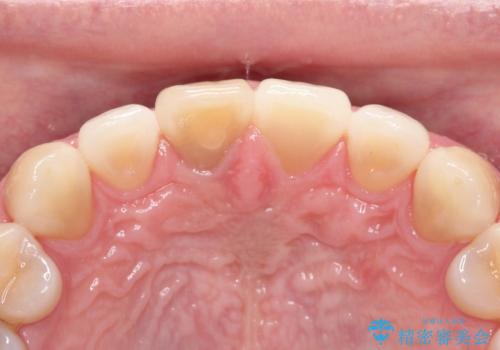

【前歯の被せ物】オールセラミッククラウン(エクセレント)

- 空隙歯列と前歯の変色を主訴に来院されました。

空隙歯列を矯正にて改善した後に歯冠修復を行なっております。

上顎前歯は根管治療後にオールセラミッククラウン(エクセレント)で修復を行なっております。